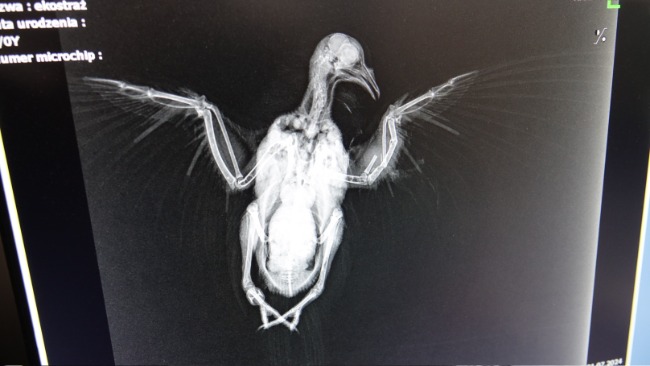

Właściciela posesji miała rację - ptak ma w sobie świeży śrut, który rozerwał mu jedno skrzydło, które jest całkowicie połamane. Dobrze się przyglądając, można zobaczyć ranę wlotową 😭😭😭

⚠️ Cel był celny. Tak jak okrucieństwo,, sadyzm, brak empatii, zwykłego zwyrodnialca, który z zabawy uczynić sobie okrutną rozrywkę. Oczywiście - z uwagi na dobre rokowania oraz sadystyczną krzywdę, której doznał, będziemy ratowali jego życie i sprawność. Patrzcie, jaki jest piękny i dobry dla ludzi.

WESPRZYJ RATOWANIE UMYŚLNIE OKALECZONEO GOŁĘBIA HODOWLANEGO. CZEKA GO OPERACJA. PTAK PRZEBYWA POD OPIEKĄ WROCŁAWSKIEJ EKOSTRAŻY.